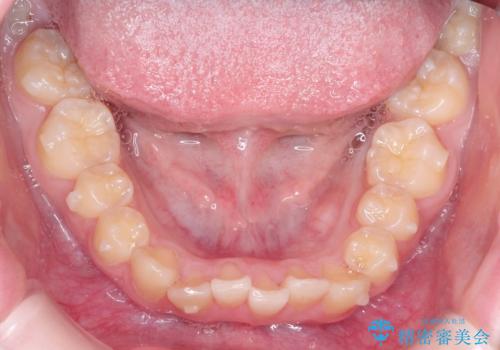

なるべく通院回数を減らして矯正したい インビザラインでのガタガタ矯正

ワイヤー矯正が1か月に1回程度来院が必要なのと比較すると、2-3か月に1回の来院でもよいので(症例によります)、通院回数を減らすことができて、患者様の負担を減らすことができます。